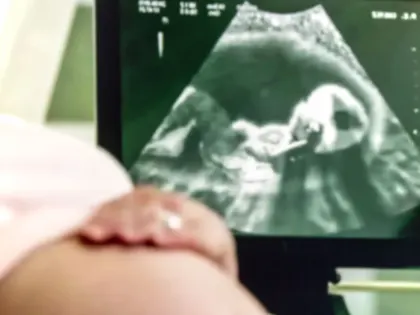

В России хотят тестировать будущих родителей на генетические риски

Путин поручил ввести тестирование будущих родителей на генетические риски Фото:

В России будущим родителям предложат тесты на генетические риски. В ЯНАО планирующие детей пары проходят репродуктивную диспансеризацию

Фото: New Africa/Shutterstock/Fotodom До 15 мая 2025 года федеральное правительство и региональные власти должны представить планы по реализации программы генетического тестирования пар, которые планируют рождение детей,